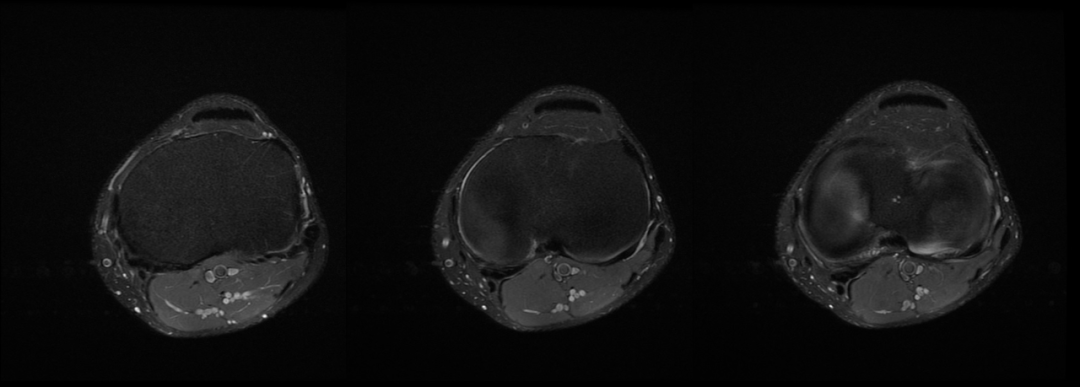

主诉:右膝关节外侧反复疼痛不适半年余,近一个星期疼痛加重。现病史:患者右膝关节外侧间歇性疼痛不适半年余,近一个星期疼痛加重,屈膝时明显,门诊行膝关节 X 线片检查,未见明显异常。患者否认手术史/外伤史。为进一步明确情况,我们建议患者行膝关节磁共振检查;图像如下:T1

T2 压脂

冠状位

轴位

大家是否发现什么异常?该患者是膝外侧疼痛不适的症状,我们重点观察了外侧半月板及外侧副韧带,但是我们发现是正常的;

但是我们发现有一个地方信号不对;

大家发现了没有?那这是什么呢?

那么我们刚刚看到信号增高的就是髂胫束,排除了半月板和外侧副韧带的问题,那么膝关节外侧疼痛是不是这个原因导致的呢?

1 T2WI PD 序列上可以显示靠近股骨外侧髁与髂胫束之间的信号增高,边界不清,外侧滑膜增厚;

2 髂胫束靠近股骨外侧髁水平出现增厚改变,部分严重患者可以出现连续性中断;3 髂胫束表面或深部信号明显增高;4 可伴股骨外侧髁反应性骨髓水肿